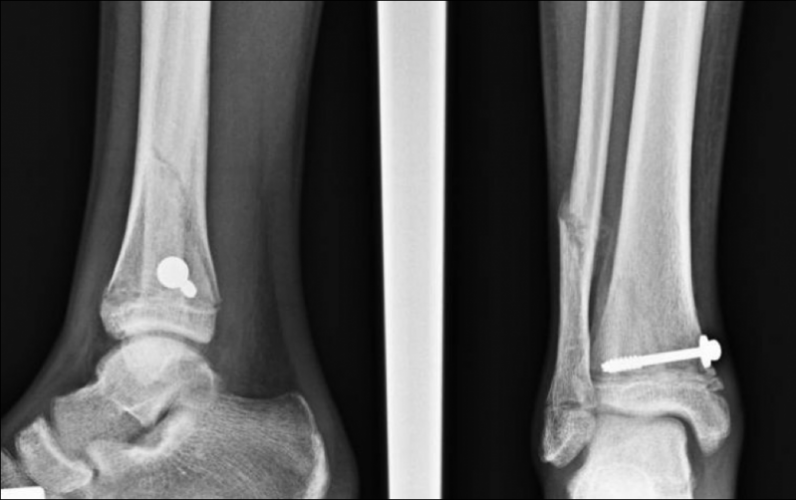

Fig 1 Rx in Ap distacco epifisario di tibia tipo II di Salter e Harris e frattura di perone

Fig. 3 Rx AP e LL 1 mese dopo l'intervento. Riduzione della frattura ottenuta mediante 1 vite cannulata con rondella.